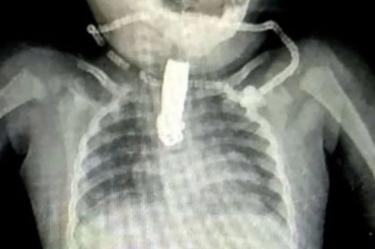

Bebé se traga cortaúñas; radiografía muestra objeto atorado

La bebé se tragó un cortaúñas y la radiografía mostró el objeto atorado en su garganta.

Una radiografía muestra el objeto atorado en la garganta de la bebé, los médicos estudiaron muchas posibilidades para retirar el objeto atorado en la garganta.

De acuerdo con los reportes, un grupo de médicos tardó varias horas en retirar el cortaúñas en una complicada cirugía.

Afortunadamente todo salió bien y la bebé ya se recupera con éxito.